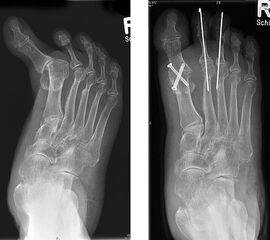

11"> Der Hallux varus Winkel  <a class=11" title="Der Hallux varus Winkel 11" srcset="/assets/images/2/4-vk3bypbg5s5x7zc.jpg 1x, /assets/images/3/4-aax2sd1hrpnrvrb.jpg 1.452x" width="270" height="240" loading="lazy">

Abbildung 3

Die bildgebende Diagnostik hilft bei der Klärung der Ätiologie und des Ausmaßes der Fehlstellung. Hierzu sind Röntgen­aufnahmen im Stand in mindestens zwei Ebenen unter Belastung des Fußes erforderlich. Mit Hilfe der belasteten Röntgenaufnahmen wird der Hallux-varus-Winkel, d. h. den Winkel zwischen der Achse der Grundphalanx der Großzehe und der Achse des ersten Mittelfußknochens bestimmt, sowie etwaige Rotationsfehlstellungen des 1. Strahls verifiziert. Eventuelle knöcherne Fehlanlagen bei kongenitalen Deformitäten können hierdurch ebenfalls verifiziert werden.

Weitere Beurteilungskriterien sind:

• degenerative Veränderungen des MTP I

• Kongruenz des MTP I- Gelenkes

• Form und Stellung des Mittelfußköpfchens I

• Ausprägung der Pseudoexostose.

• PASA-Winkel, d. h. der periphere Artikulationswinkel des Großzehengrundgelenkes.

Zur Klärung der Ätiologie wird der intermetatarsale Winkel zwischen Os metatarsale I und II bestimmt. Ist dieser kleiner als 5° oder gar negativ, ist eine Varusstellung der Großzehe oft die Folge.

Am Röntgenbild des belasteten Fußes bestimmt man die Lage der Sesambeine zum 1. Mittelfußköpfchen.

Anhand der Röntgenaufnahme lassen sich die Folgen einer eventuellen Voroperation bestimmen, wie z. B. die Stellung des ersten Mittelfußköpfchens, des ersten Metatarsale nach Korrekturen der Achse bei einer Hallux-valgus-Operation. Mitunter bestehen Nekrosen des Mittelfußköpfchens oder eine übermässige Resektionen der Pseudoexostose. Auch die Länge des 1. Metatarsale kann von Interesse sein, z. B. nach einer Lapidusarthrodese (Johnson 1994).